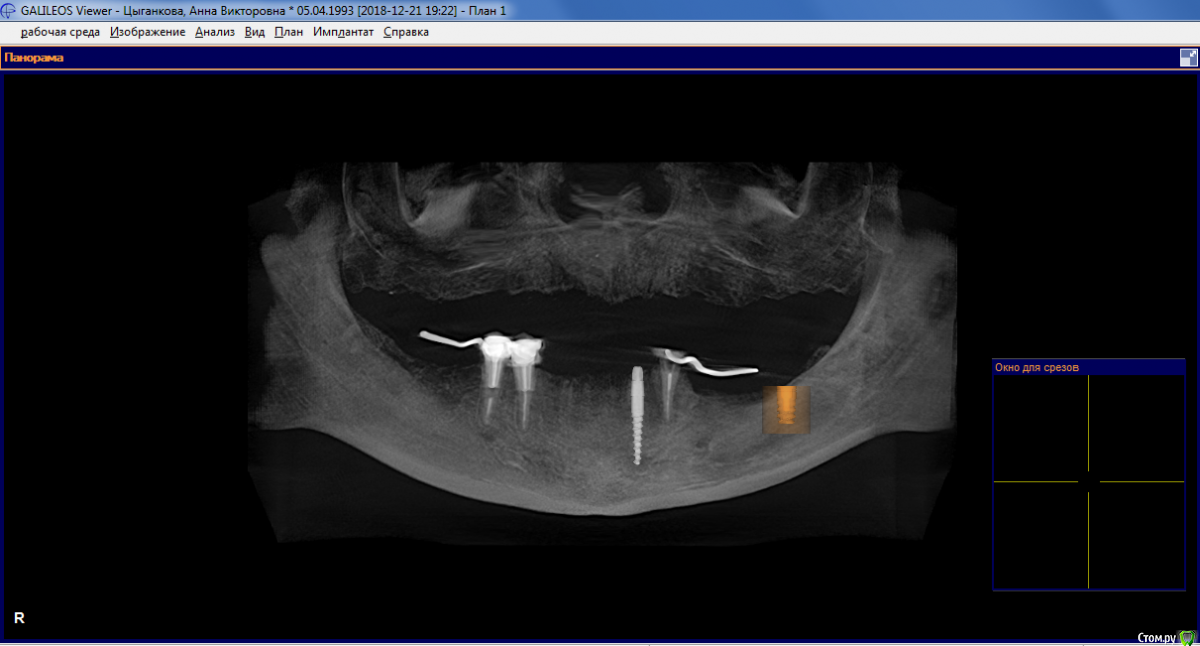

Фалина Опубликовано 25 июня, 2019 Поделиться Опубликовано 25 июня, 2019 Здравствуйте. Планируется удалить оставшиеся зубы и поставить на нижнюю челюсть 8 имплантов. Из них 3 шт. диаметром 4,2 мм и 5 шт. диаметром 3,2 мм. Из тех же восьми 5 шт. длиной 8 мм и 3 шт. длиной 11-13 мм. В самом узком месте планируется костная пластика.Два вопроса:1. На таких тонких имплантах правда будет нормально стоять постоянный протез? Их много, но они какие-то маленькие, я немного беспокоюсь.2. Почему мне нельзя после установки имплантов носить временный съёмный протез? Я гуглила, но так и не поняла. Разве он не называется временным именно потому, что его надевают на время заживления? Вроде как всем можно, кроме тех, у кого воспаление или плохая гигиена, так почему же мне нельзя?Насколько я поняла, бывает так называемая одноэтапная имплантация с немедленной нагрузкой, которую можно не всем. Но я на неё не претендую, я хочу всего лишь простой съёмный протез на время заживления. Очень не хочется ходить без зубов целых три месяца, и я не понимаю, почему от меня это требуют. Ссылка на комментарий

AndyAndy Опубликовано 25 июня, 2019 Поделиться Опубликовано 25 июня, 2019 Отвечу на второй вопрос: в вашем случае временный съемный протез является скорее противопоказанием, так как планируется костная пластика. Данный вид протеза оказывает давление и на мягкие, и на твёрдые ткани, что в вашем случае может привести к неблагоприятным последствиям, вплоть до потери объёма костнопластического материала. Заживление мягких тканей также будет протекать не лучшим образом. По первому вопросу: вашему доктору виднее, какой тип конструкции планируется, какое костное предложение имеется и, соответственно, как это все будет функционировать на данных имплантатах Ссылка на комментарий

колесников Опубликовано 26 июня, 2019 Поделиться Опубликовано 26 июня, 2019 4.2 -хороший диаметр. С таким количеством имплантов вполне можно расчитывать на немедленную нагрузку Ссылка на комментарий